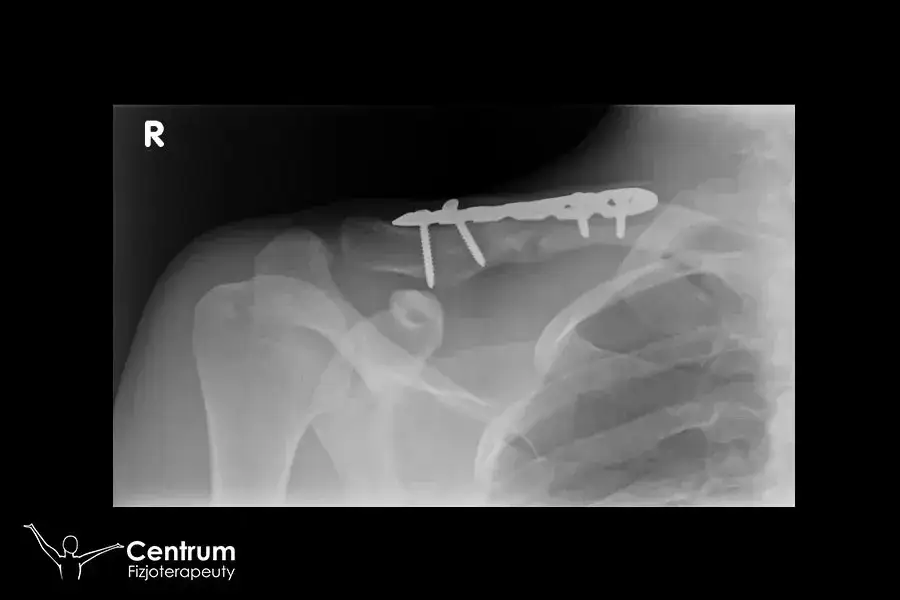

Regeneracja po złamaniu obojczyka z przemieszczeniem jest bardziej skomplikowanym procesem niż w przypadku prostych złamań. Czas rehabilitacji w takich przypadkach zazwyczaj wynosi od 6 do 12 miesięcy. Po interwencji chirurgicznej, takiej jak zastosowanie płytek i śrub, pacjenci mogą rozpocząć ruchy ramieniem już kilka dni po zabiegu. Jednak pełna rehabilitacja wymaga więcej czasu i zaangażowania.

Metoda leczenia ma kluczowy wpływ na czas trwania rehabilitacji po złamaniu obojczyka. Złamania, które wymagają interwencji chirurgicznej, zazwyczaj prowadzą do dłuższego okresu regeneracji. Po operacji, pacjenci mogą rozpocząć rehabilitację już po kilku tygodniach, jednak pełne odzyskanie sprawności może zająć od 6 do 12 miesięcy. W przeciwieństwie do tego, niechirurgiczne metody leczenia, takie jak unieruchomienie, mogą skrócić czas rehabilitacji do 3-6 miesięcy, ale wymagają starannego monitorowania.

W przypadku zabiegów chirurgicznych, takich jak zastosowanie płytek i śrub, pacjenci często doświadczają bardziej skomplikowanego procesu powrotu do zdrowia. W takich sytuacjach, rehabilitacja musi być dostosowana do specyficznych potrzeb pacjenta, co może wydłużyć czas potrzebny na osiągnięcie pełnej sprawności. Dlatego wybór metody leczenia jest kluczowy dla określenia, jak długo trwa rehabilitacja po złamaniu obojczyka.Rola stanu zdrowia pacjenta w procesie regeneracji